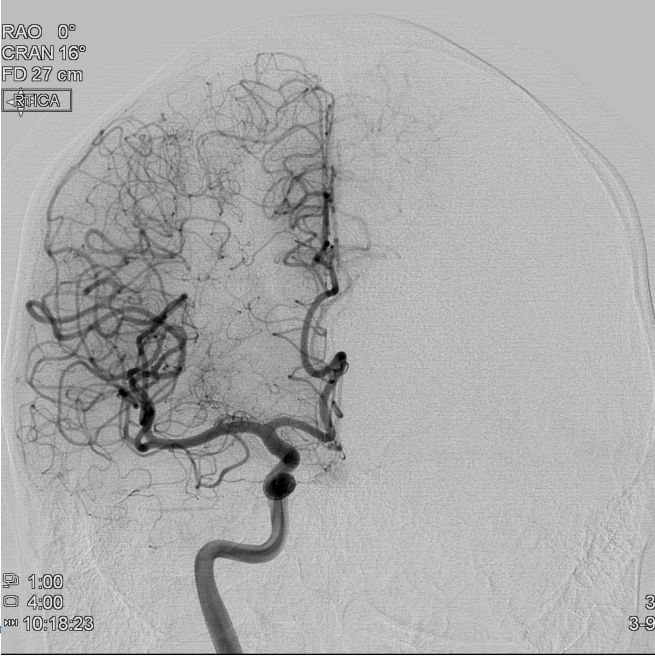

**Case 8 Q# 1 of 3** * 19 y/o man collapsed playing basketball. He was having a seizure consisting of right arm shaking and then fell to the ground without protecting himself. * On arrival noted to have weakness on his right side, reactive pupils, positive corneals and cough. Not following commands or moving spontaneously. * Vitals: 220/120, HR 45, RR 12 (intubated) * CT is attached What about the CT helps you **rule out** contusion secondary to his fall as the cause of his lesion?

The lesion is **located** in the middle of the cortex. Contusion damage typically occurs around the **frontal pole, occipital pole, or temportal tips** of the brain

**Case 8 Q# 2 of 3** * 19 y/o man collapsed playing basketball. He was having a seizure consisting of right arm shaking and then fell to the ground without protecting himself. * On arrival noted to have weakness on his right side, reactive pupils, positive corneals and cough. Not following commands or moving spontaneously. * Vitals: 220/120, HR 45, RR 12 (intubated) * CT is attached Looking at his CT, what is the underlying brain lesion that has now ruptured to cause his seizure?

Arteriovenous malformation (AVM)

**Case 8 Q# 3 of 3** * 19 y/o man collapsed playing basketball. He was having a seizure consisting of right arm shaking and then fell to the ground without protecting himself. * On arrival noted to have weakness on his right side, reactive pupils, positive corneals and cough. Not following commands or moving spontaneously. * Vitals: 220/120, HR 45, RR 12 (intubated) * CT is attached What further brain injury is this man at imminent risk for? How can you tell?

**Brain Herniation**. **Extreme HTN + low HR = Cushing Reflex**, which is noted in patients with increased ICP and can suggest imminent herniation.